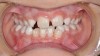

Mouth breathing has also been associated with dental malocclusions in children.2 Zicari and colleagues' analysis of 71, 6- to 12-year-old mouth breathing children revealed a 72.5% incidence of reduced transverse diameter of the maxilla and increased vertical dimension, a 32.5% incidence of cross bite, a 43.7% incidence of skeletal class II malocclusions, and a 90% incidence of atypical swallowing patterns. The results showed a strong correlation between oral breathing and malocclusions, which manifests as both dentoskeletal and functional alterations, leading to a dysfunctional malocclusive pattern (Figure 1 through Figure 3). The study concludes that “this dysfunctional malocclusive pattern makes it clear that the association between oral breathing and dental malocclusions represents a self-perpetuating vicious circle in which it is difficult to establish if the primary alteration is respiratory or maxillofacial. Regardless, the problem needs to be addressed and solved through the close interaction of the pediatrician, otorhinolaryngologist, allergologist, and orthodontist.”

(2.) In children, mouth breathing with low tongue posture can result in narrow maxillary arches, dental crowding, tongue scalloping, and anterior open bites. Images courtesy of Kevin Boyd, DDS, MSc.

Figure 2